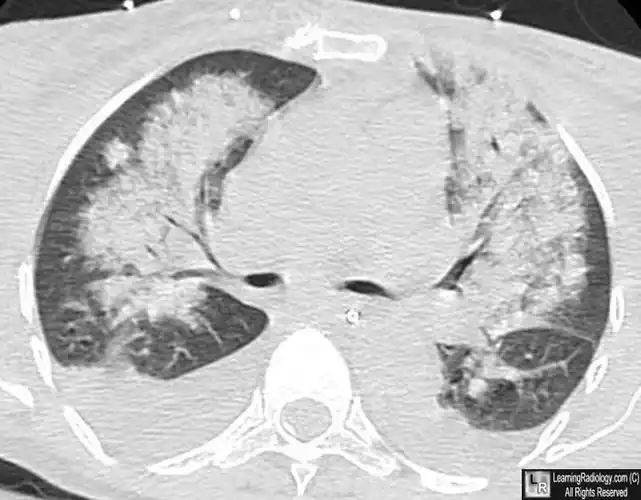

其x线可表现为肺泡性或间质性肺水肿.↑ 男性,65岁.肾衰肺水肿

图4 肺泡性水肿ct扫描.双侧肺门气道病变几乎对称(有空气支气管征).

f,45,心源性肺泡性肺水肿.双肺内中带分布.